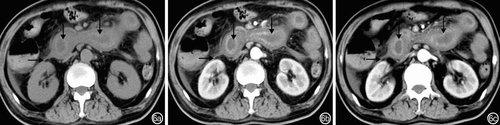

十二指肠癌患者CT检查主要表现为局限性中重度肠壁不均匀性增厚,密度不均匀,局部可见软组织包块,病变肠壁明显不均匀强化(图4);肠外主要表现为肠腔偏心或环形狭窄、直肠周围脂肪间隙消失、腹股沟、腹膜后或肠系膜淋巴结肿大、腹腔积液,回盲部肝转移癌偶尔并发肠套叠和肠梗阻。(点击图片可查看原图)

图4 十二指肠癌患者CT检查特征:十二指肠壁明显不均匀性增厚(←)4a:平扫肠壁密度不均匀;4b:动脉期肠壁明显不均匀强化;4c:静脉期肠壁明显均匀强化

肝硬化门静脉高压症患者CT检查结果主要表现为胃、小肠弥漫性轻度环状向心性增厚、明显不均匀强化;肠外主要表现为肝硬化、脾肿大、食管胃底静脉曲张、腹腔积液(图5)。(点击图片可查看原图)

图5 肝硬化门静脉高压症CT检查特征 5a:平扫小肠壁弥漫性轻度增厚(←);5b:动脉期肝硬化、腹腔积液(→)、食管静脉曲张(↓);5c:静脉期小肠壁增厚且明显不均匀强化(←)